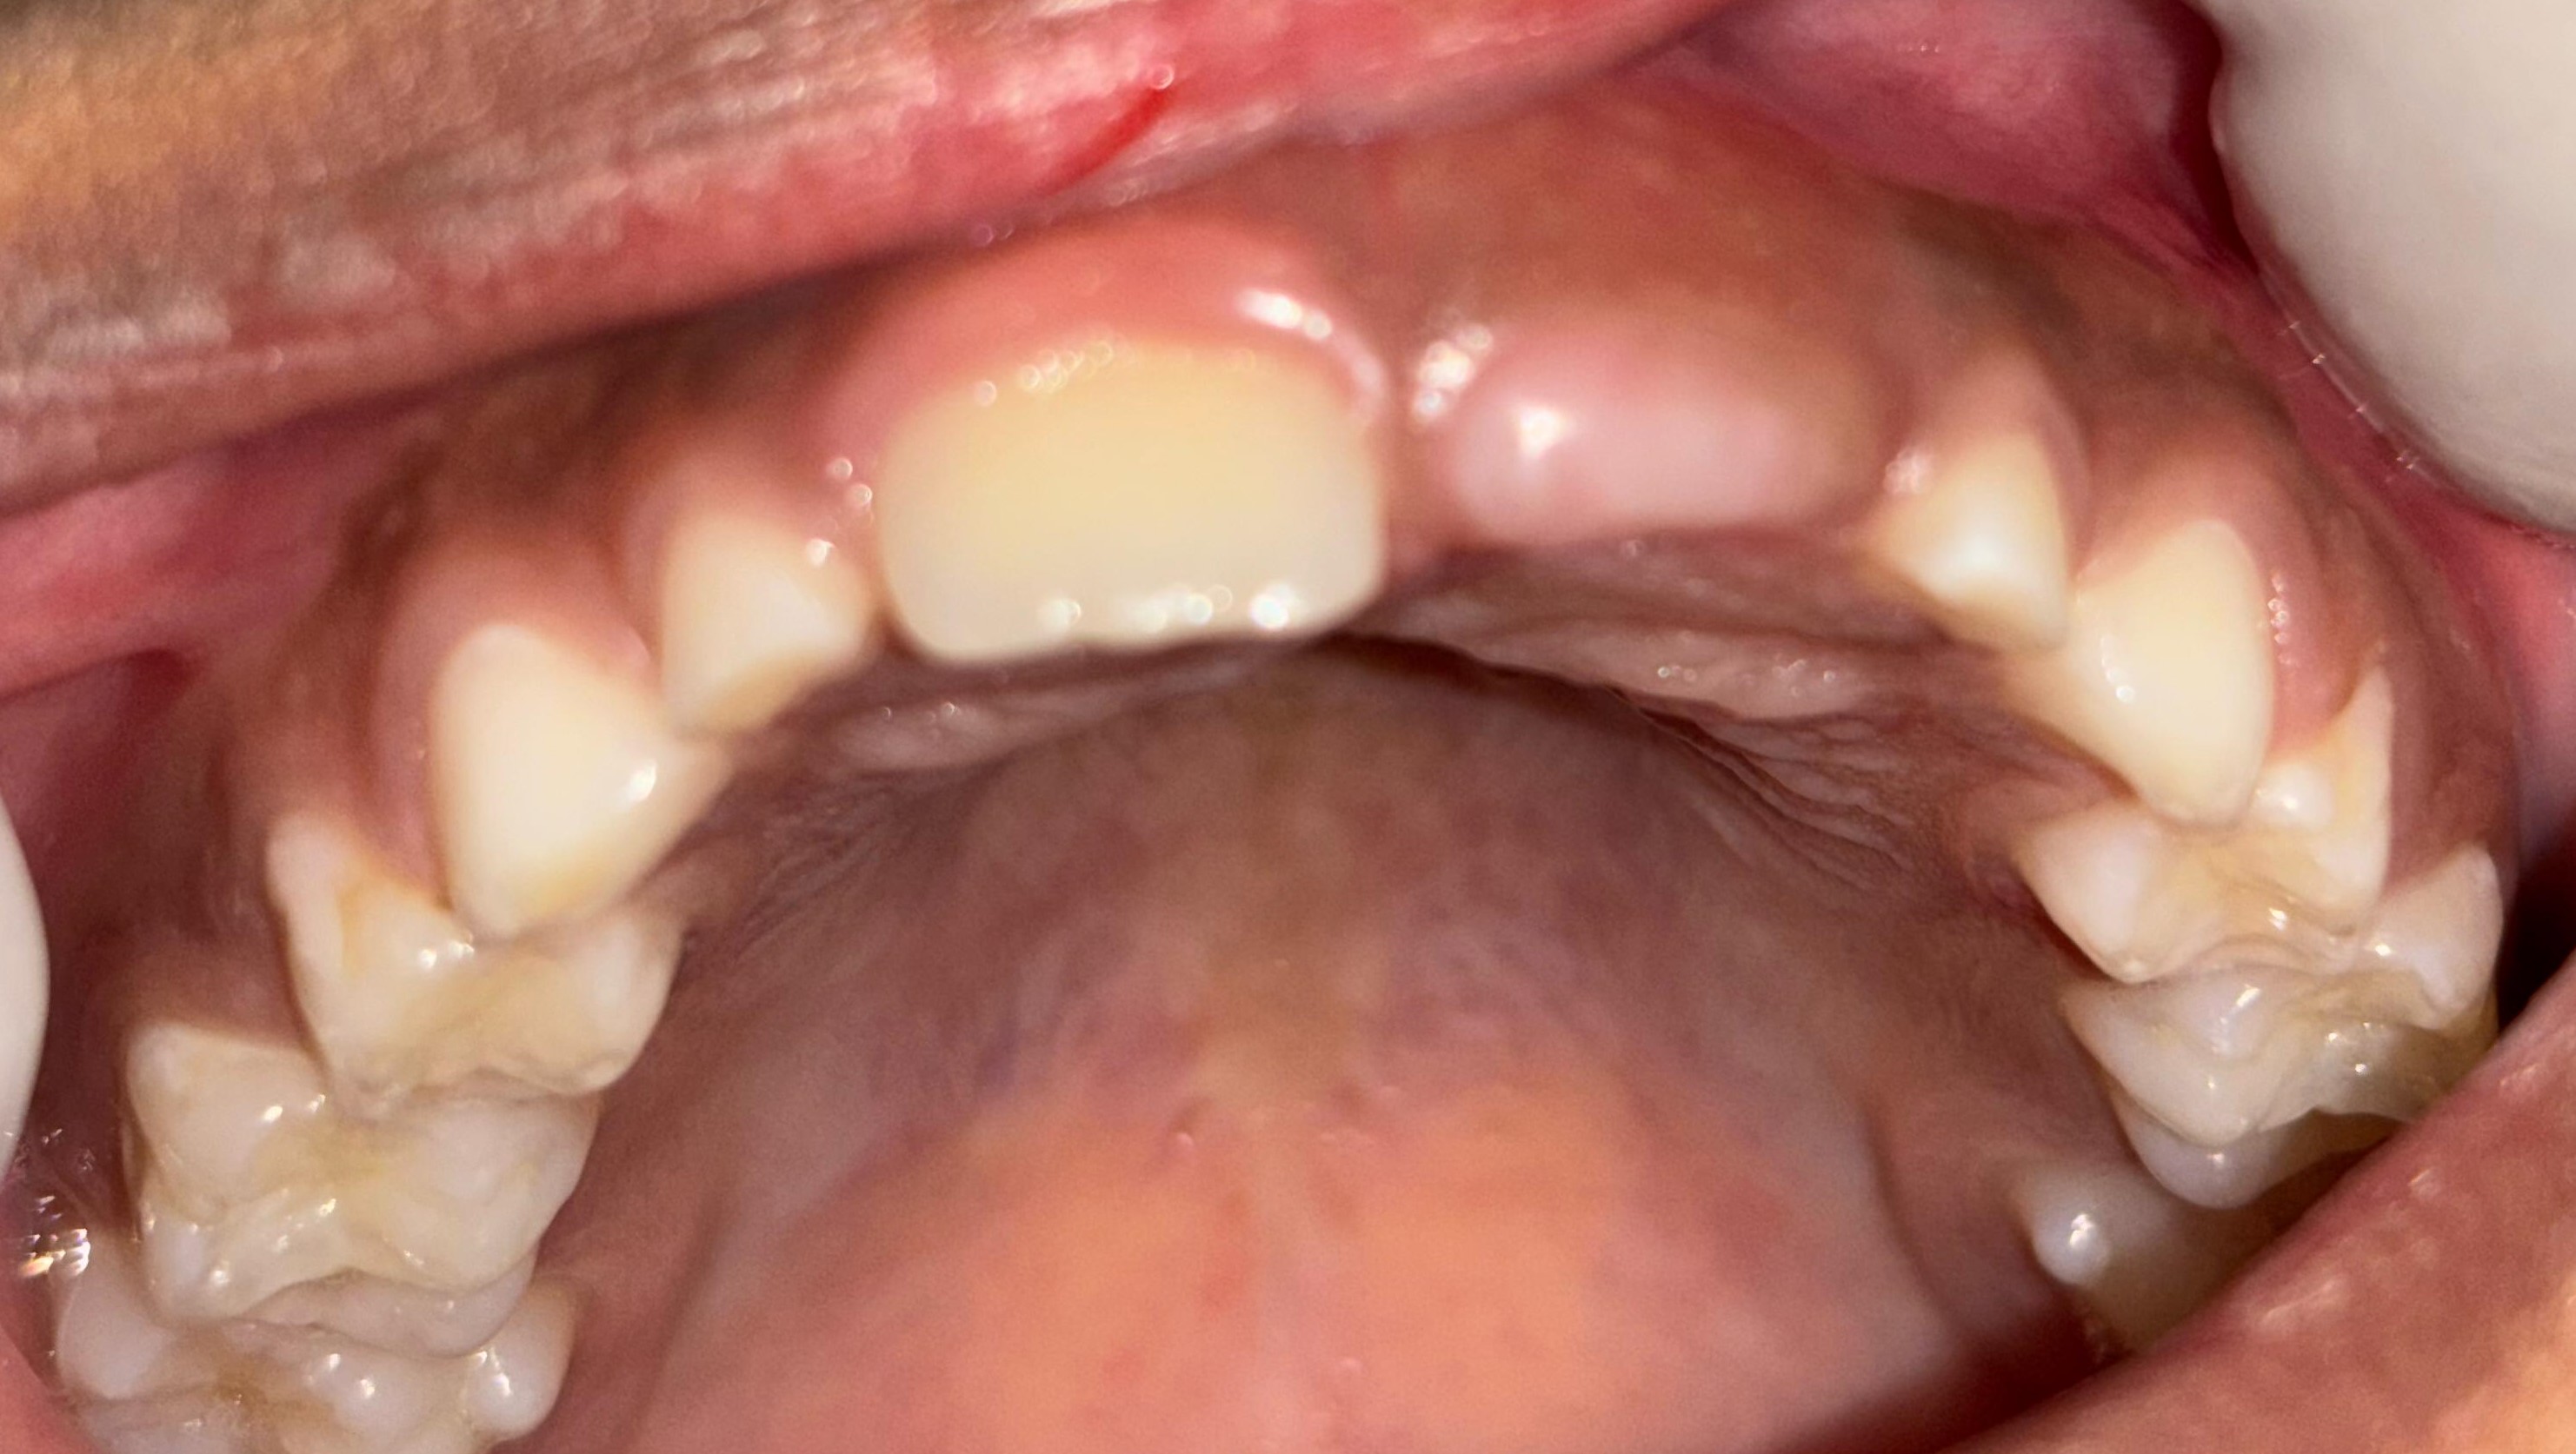

After After

Before Before